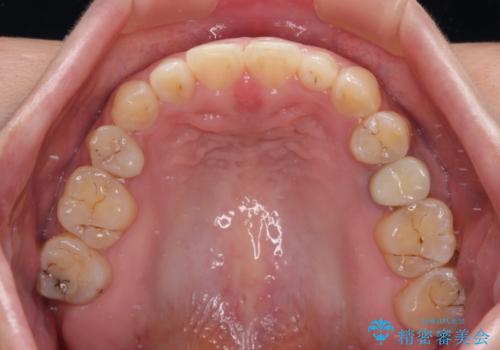

隙間の空いた歯列とボロボロの乳歯 インプラント治療と矯正治療

歯列はワイヤー矯正にて改善することとしましたが、上下歯列にも隙間があったので、舌の突出癖を改善するトレーニングを徹底的に行うこととしました。

舌の突出癖改善のトレーニングが全くうまくできず、治療期間が長期化しました。

早く治療を終えたいとの要望があり、トレーニング次第と伝えるとようやく練習をするようになり、その後は速やかに上下の隙間が改善されました。